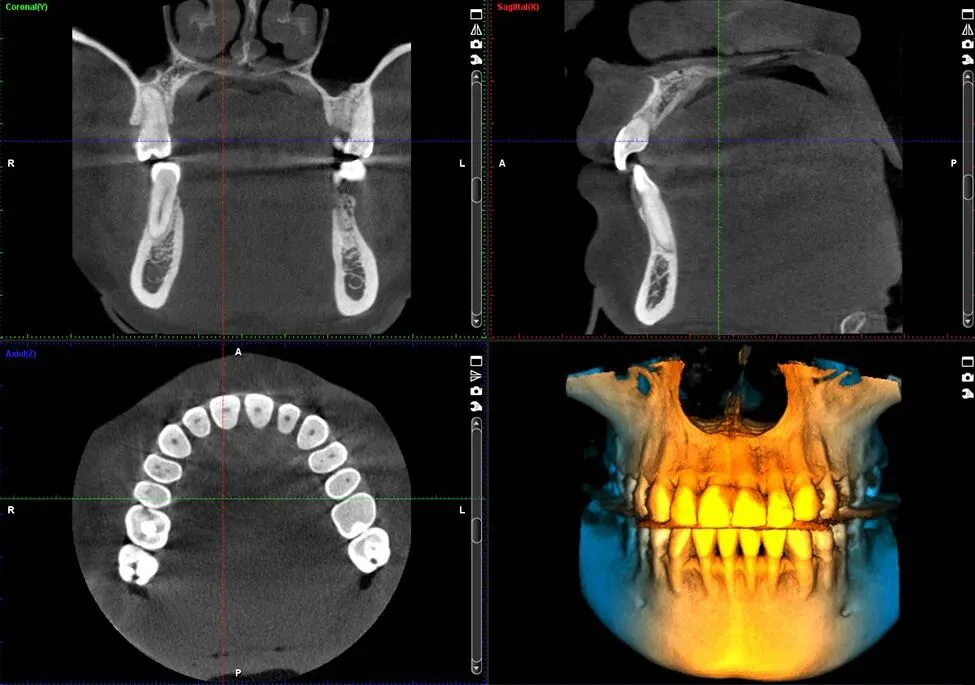

Planmeca的ProMax 3D CBCT成像机,零售价约10万美元,辐射剂量低(20μSv/扫描),分辨率0.1mm,在芬兰和荷兰诊所使用,提供全景和3D视图,支持种植规划,体现了基础设施配套的进步。